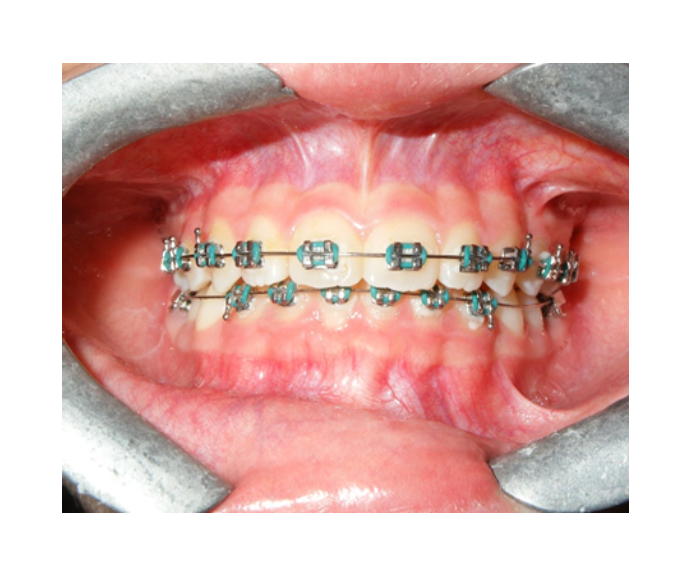

Ortodoncia

temprana

Ortodoncia en

Adultos